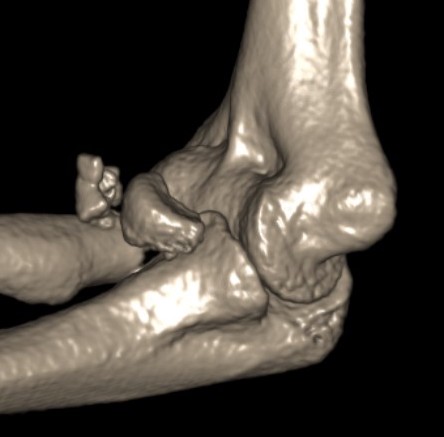

Overstuffing

| Lesser sigmoid notch | Symmetry of ulnohumeral joint |

|---|---|

|

Radial head shoulder articulate with lesser notch

Ensure no gapping of lateral ulnohumeral joint |

![]() |

- cadaveric study

- increased medial ulno-humeral joint line gapping with overlengthening of 6 or 8 mm

- increased lateral ulno-humeral joint line gapping with overlengthening of 2 mm